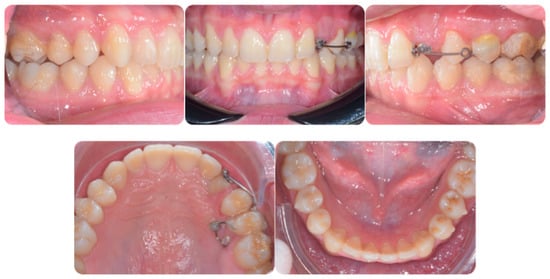

Torque finishing with aligners is the last stage of the treatment, which requires another refinement stage to obtain proper torque and inclination (Figure 6); in this case, a further stage of 18 aligners was necessary. The final occlusion is shown on Figure 7. The final X-ray analysis is presented on Figure 8.

Figure 6.

Progress of treatment after canine recovery and before aligner second phase.

Figure 7.

Post-treatment intraoral pictures after 18 months of treatment.